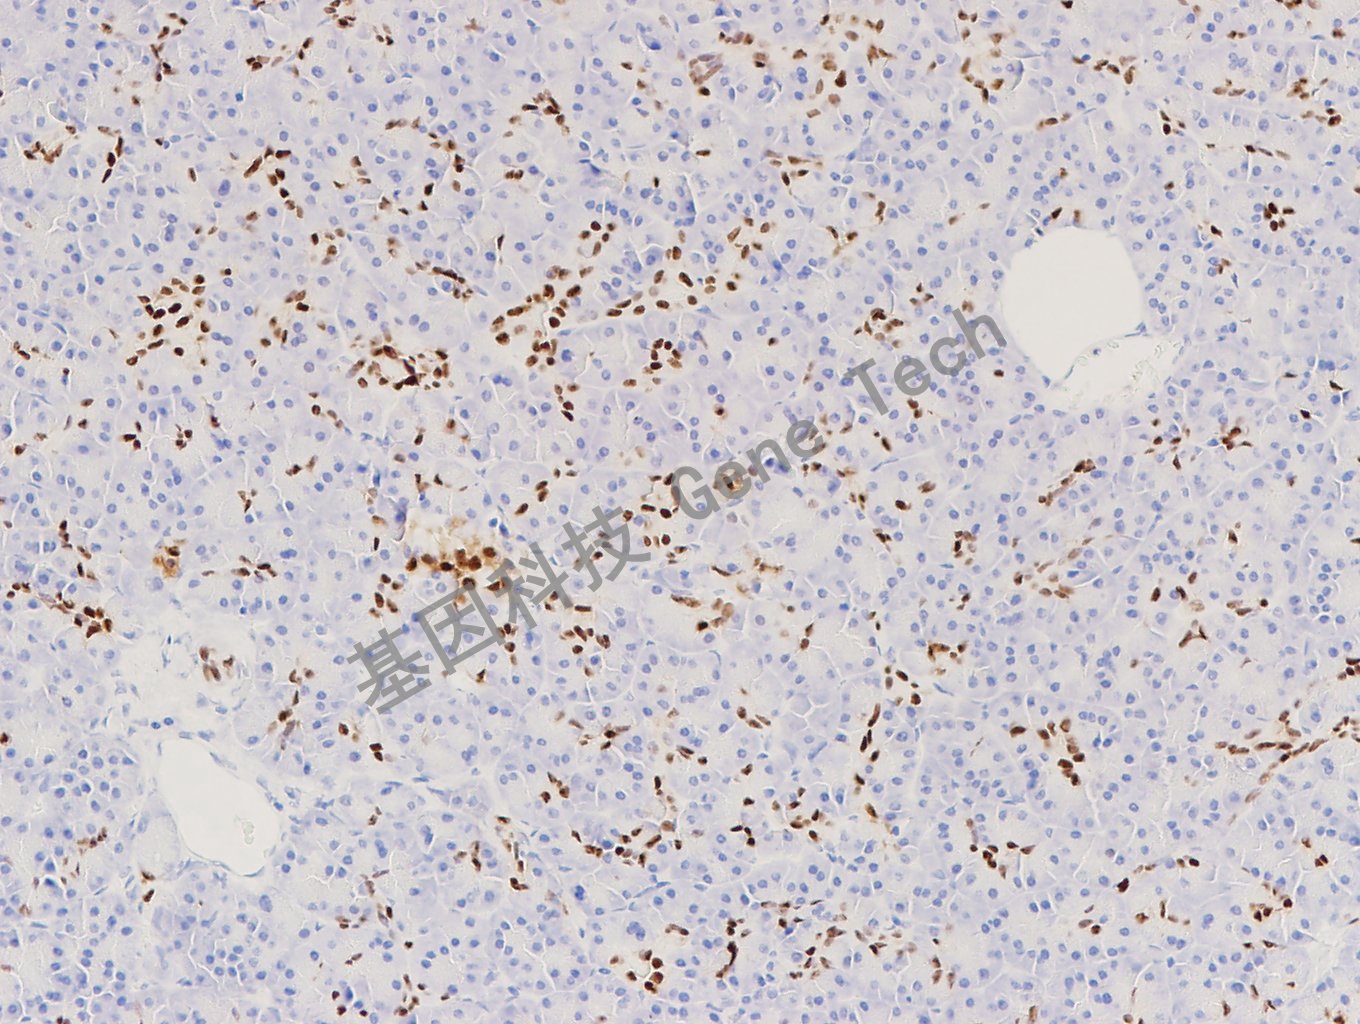

| 預(yù)處理:高pH熱修復(fù) | 陽性部位:細(xì)胞核 | 陽性對照:胰腺 |

| 簡介:PDX1 (Pancreatic and duodenal homeobox 1)又稱胰島素啟動因子1,是胰腺發(fā)育和 β 細(xì)胞成熟所必需的轉(zhuǎn)錄因子。PDX-1 基因突變已被證明可導(dǎo)致胰腺不發(fā)育、年輕人成年型糖尿病和 II 型糖尿病。PDX1 最初在胚胎的腸區(qū)表達(dá),并選擇性地在成人內(nèi)分泌腺中表達(dá),如胰腺 β- 細(xì)胞、十二指腸的布倫內(nèi)氏腺和胃的幽門內(nèi)分泌細(xì)胞。在胰腺中,PDX1可以在不成熟的外分泌細(xì)胞和導(dǎo)管細(xì)胞中被檢測到。據(jù)報道,胰腺、結(jié)腸和前列腺腫瘤中的 PDX1 表達(dá)增加,提示 PDX1 可能作為這些惡性腫瘤的一種有用的生物標(biāo)志物。 | ||

| 胰腺石蠟切片,用 PDX1(GT2293)染色,細(xì)胞核陽性,DAB 顯色。 | ||